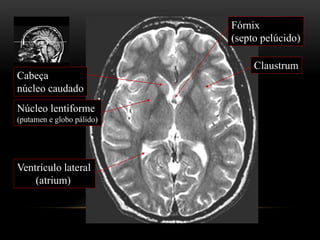

Cabeça

núcleo caudado

Núcleo lentiforme

(putamen e globo pálido)

Claustrum

Fórnix

(septo pelúcido)

Ventrículo lateral

(atrium)